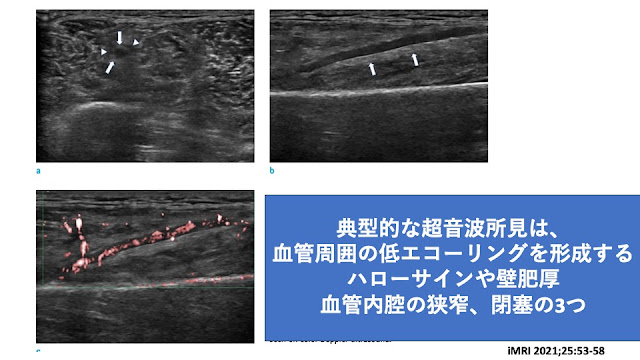

造影MRIは他の症例報告と比べてみてもそっくりな画像でした

PETでも大腿の動脈に集積を認め、下肢限局型のPNに矛盾しませんでした